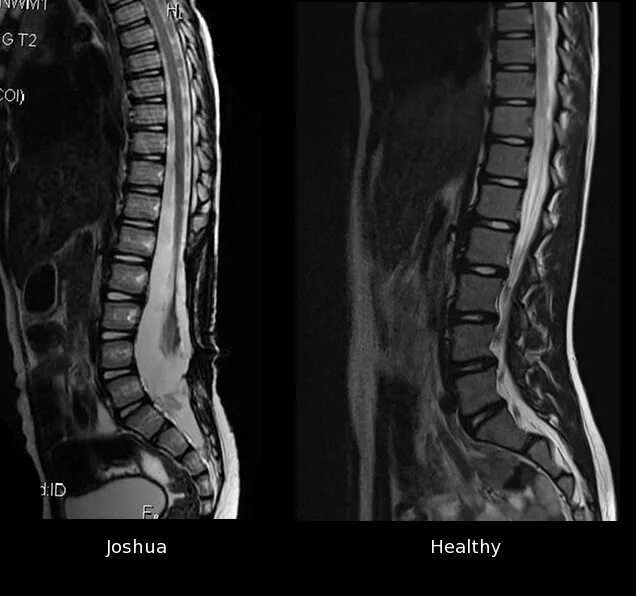

Spine mri